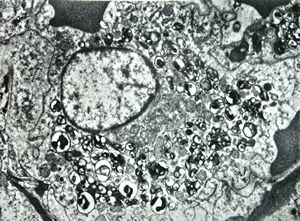

M,43y. | blood - degraded Candida (bone marrow suppression)

M,18y. | blood - clin. susp. leukemia - degraded Candida